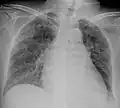

A case of miliary tuberculosis in an 82-year-old woman:

-

X-ray, 13 days after onset, showing bilateral interstitial infiltrates -

X-ray, 22 days after onset, showing extensive bilateral reticulo-nodular infiltrates -